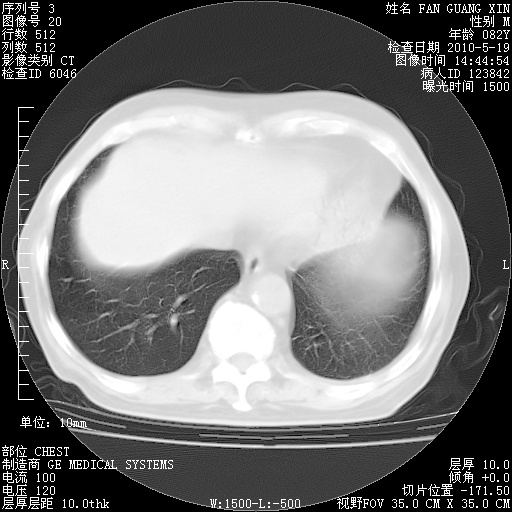

可改为口服强的松40-50mg/d治疗,若病情仍稳定,胸部阴影不再吸收可逐渐减量